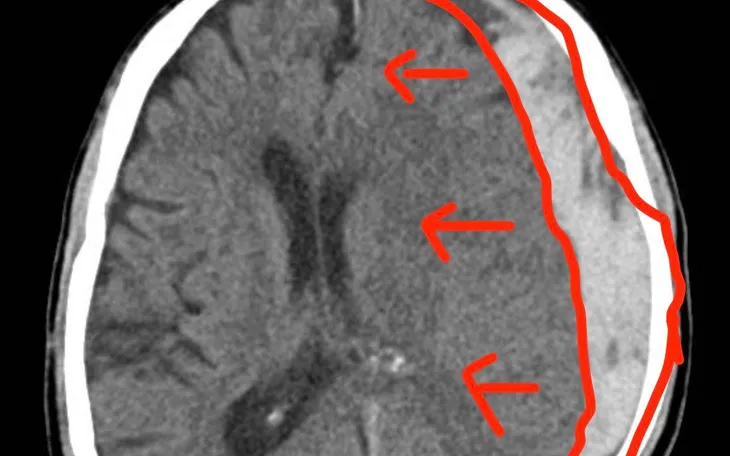

Ngay lập tức, bệnh nhân được chỉ định chụp cắt lớp vi tính sọ não. Kết quả cho thấy tụ máu dưới màng cứng hai bán cầu giai đoạn cấp, kèm tụ máu dọc liềm đại não và lều tiểu não phải, gây chèn ép não thất bên và làm lệch đường giữa 9 mm - tình trạng đe dọa tính mạng.